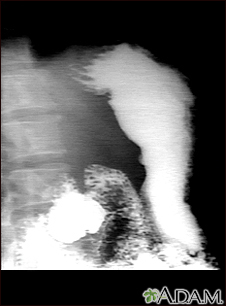

Stomach ulcer, x-rayBackStomach ulcer, x-rayThis is an example of a procedure called an upper GI series. The person swallows a substance called barium which allows for illumination of the organs in question. In this case, an ulceration is present in the stomach, seen on the right of the screen. This method is a means of diagnosing stomach ulcers as well as other anomalies along the upper gastrointestinal tract. E-mail FormEmail ResultsName:Email address:Recipients Name:Recipients address:Message: